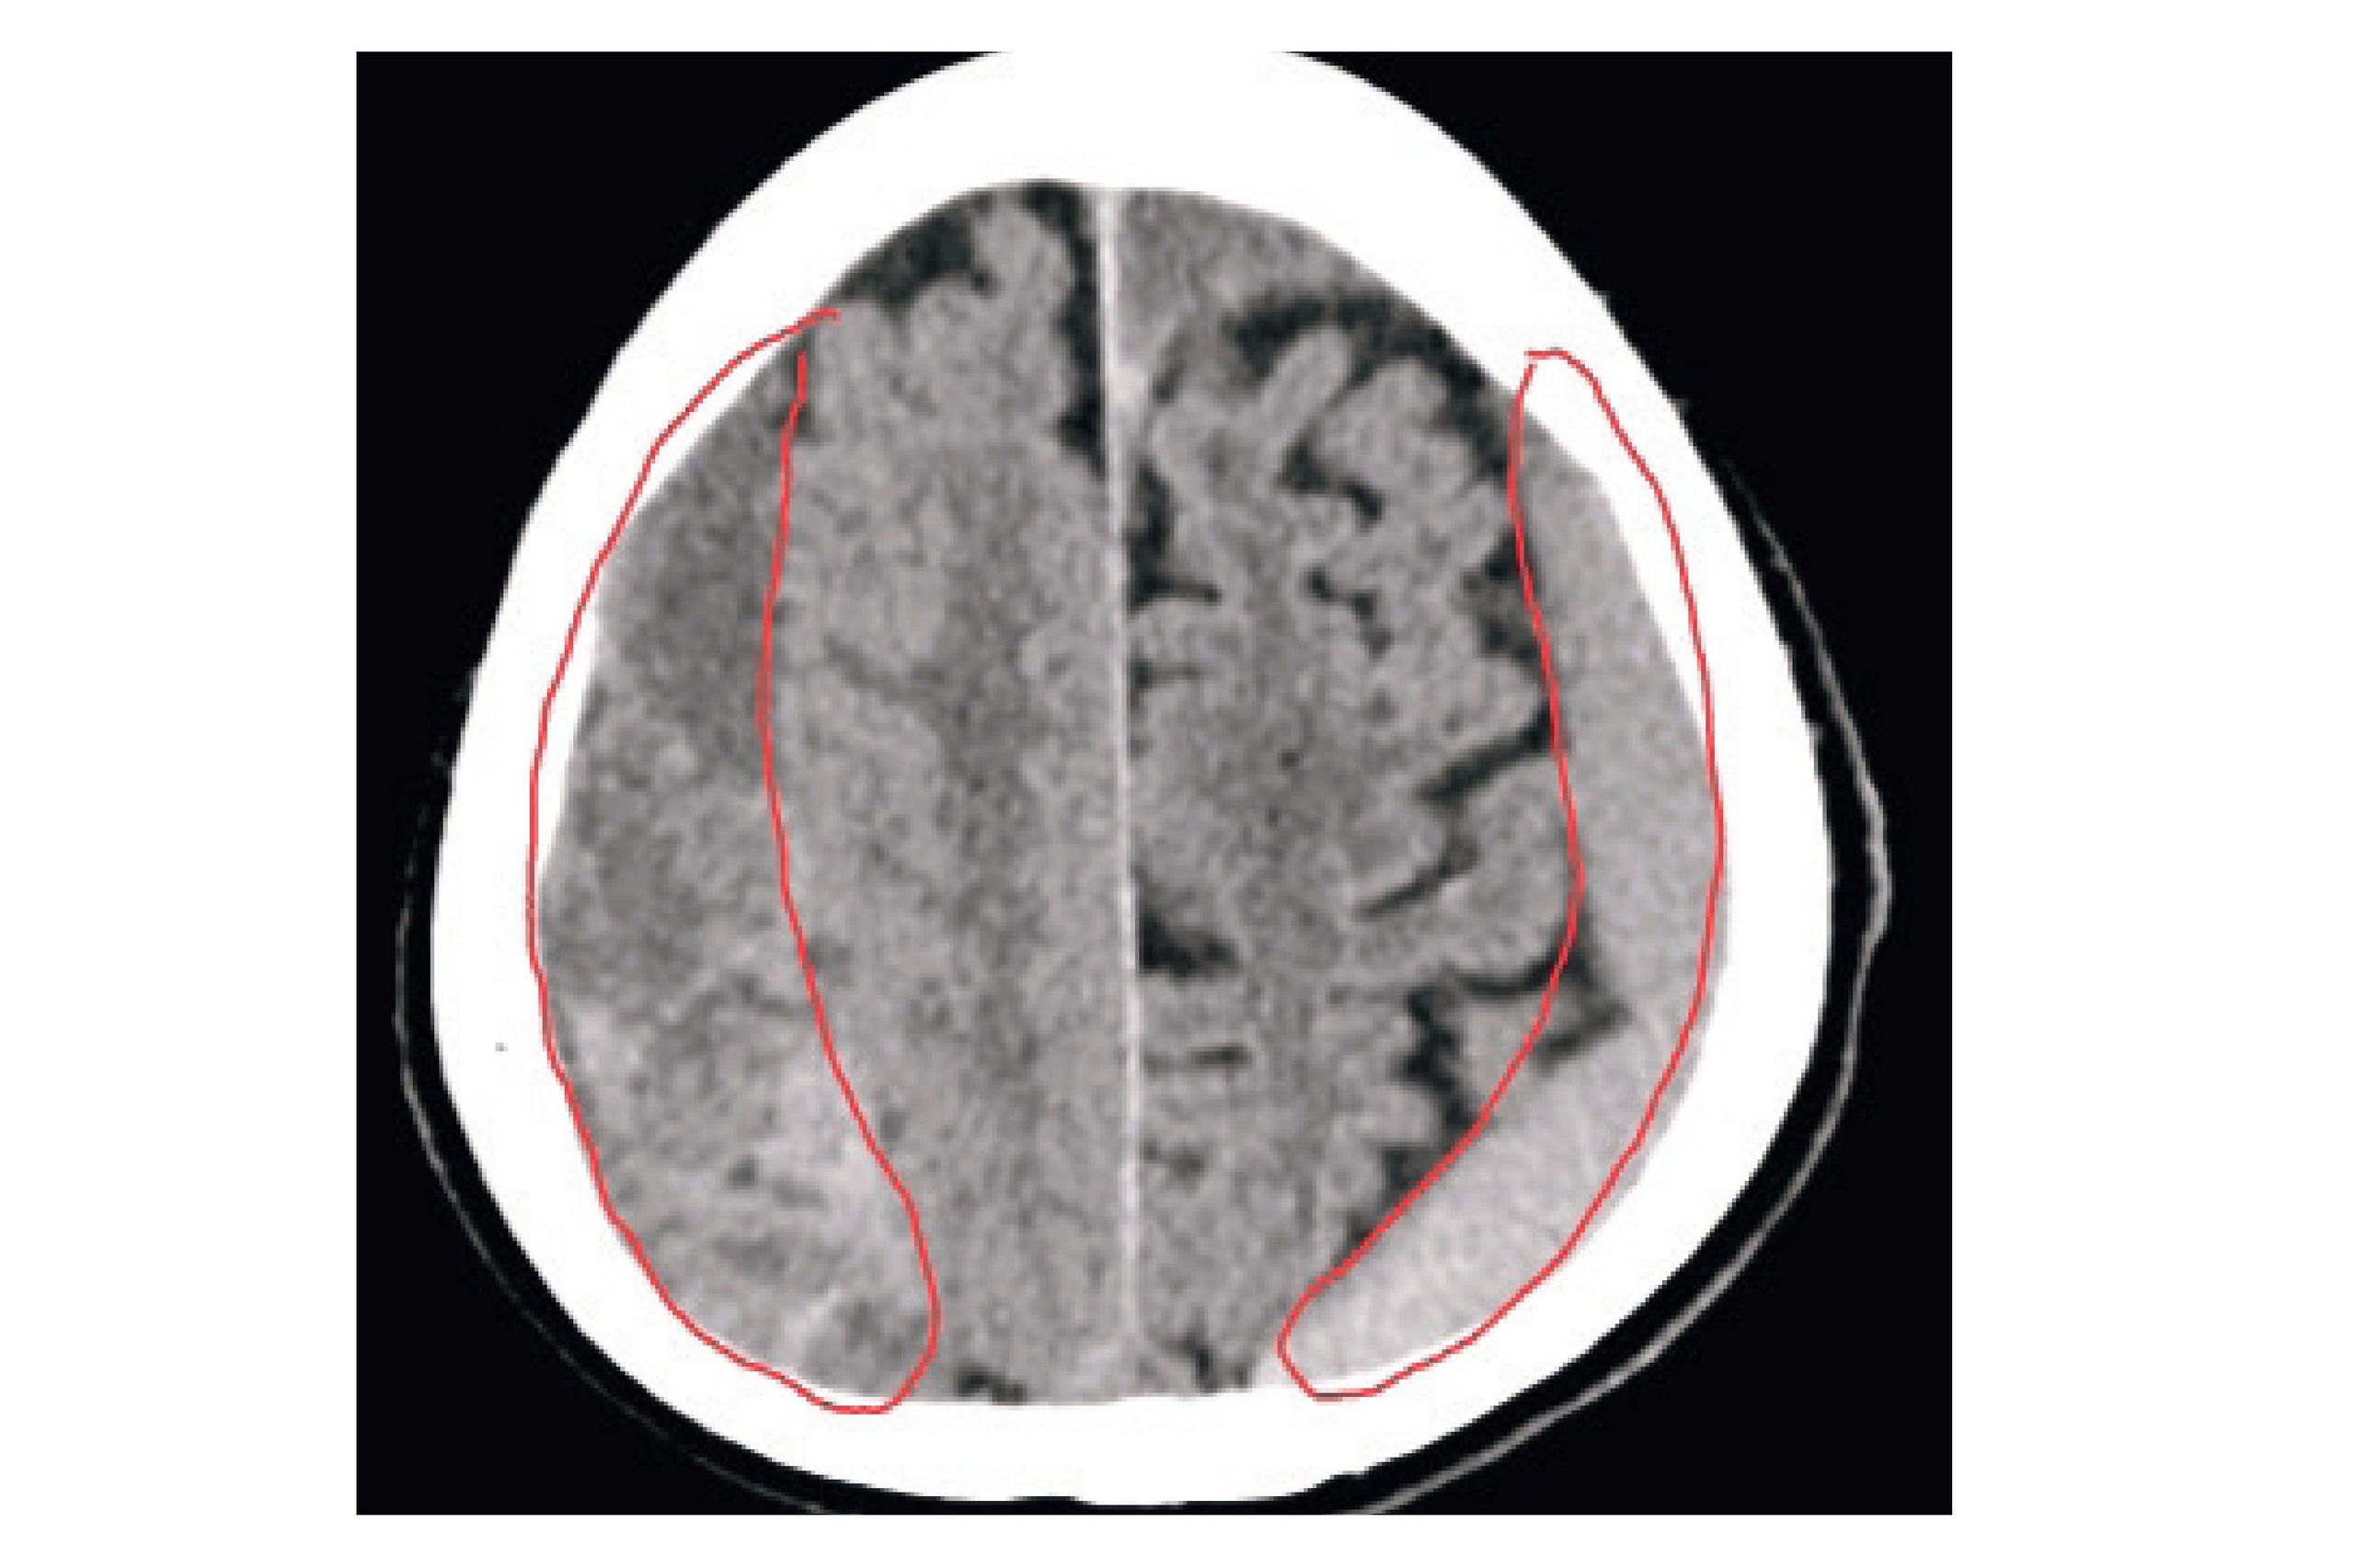

Ein „Chronisches Subduralhämatom“ (cSDH) ist eine Blutung im Kopf, die an der Gehirnoberfläche zwischen harter und weicher Hirnhaut entsteht – typischerweise bei älteren Patienten. Auslöser kann schon ein leichtes Trauma sein, begünstigt wird es durch blutverdünnende Medikamente. Das Hämatom bleibt oft lange unbemerkt, kann aber, wenn es wächst, zu neurologischen Ausfallerscheinungen, Arm-/Beinschwäche und Sprachstörungen führen.

Wenn es erforderlich wird, leitet ein Neurochirurg das Blut mittels Bohrloch und Katheter ab. Beim cSDH bilden sich im Verlauf neue Membranen, die über arterielle Gefäße versorgt werden. Diese sind jedoch spröde und instabil, was oft zu Nachblutungen führt. Eine neue Therapie ermöglicht den Verschluss der Gefäße über einen Leistenzugang und Mikrokatheter.